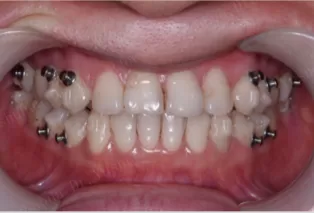

In Treatment

Intraoral photos

1. Through Smartee mandibular repositioning technology: the mandible is forced to retreat to edge-to-edge, utilizing a maxillary posterior anatomical device with occlusal splints to lock the upper and lower occlusal position.

2. During mandibular repositioning, align the teeth, level the curve of Spee and tight occlusion.